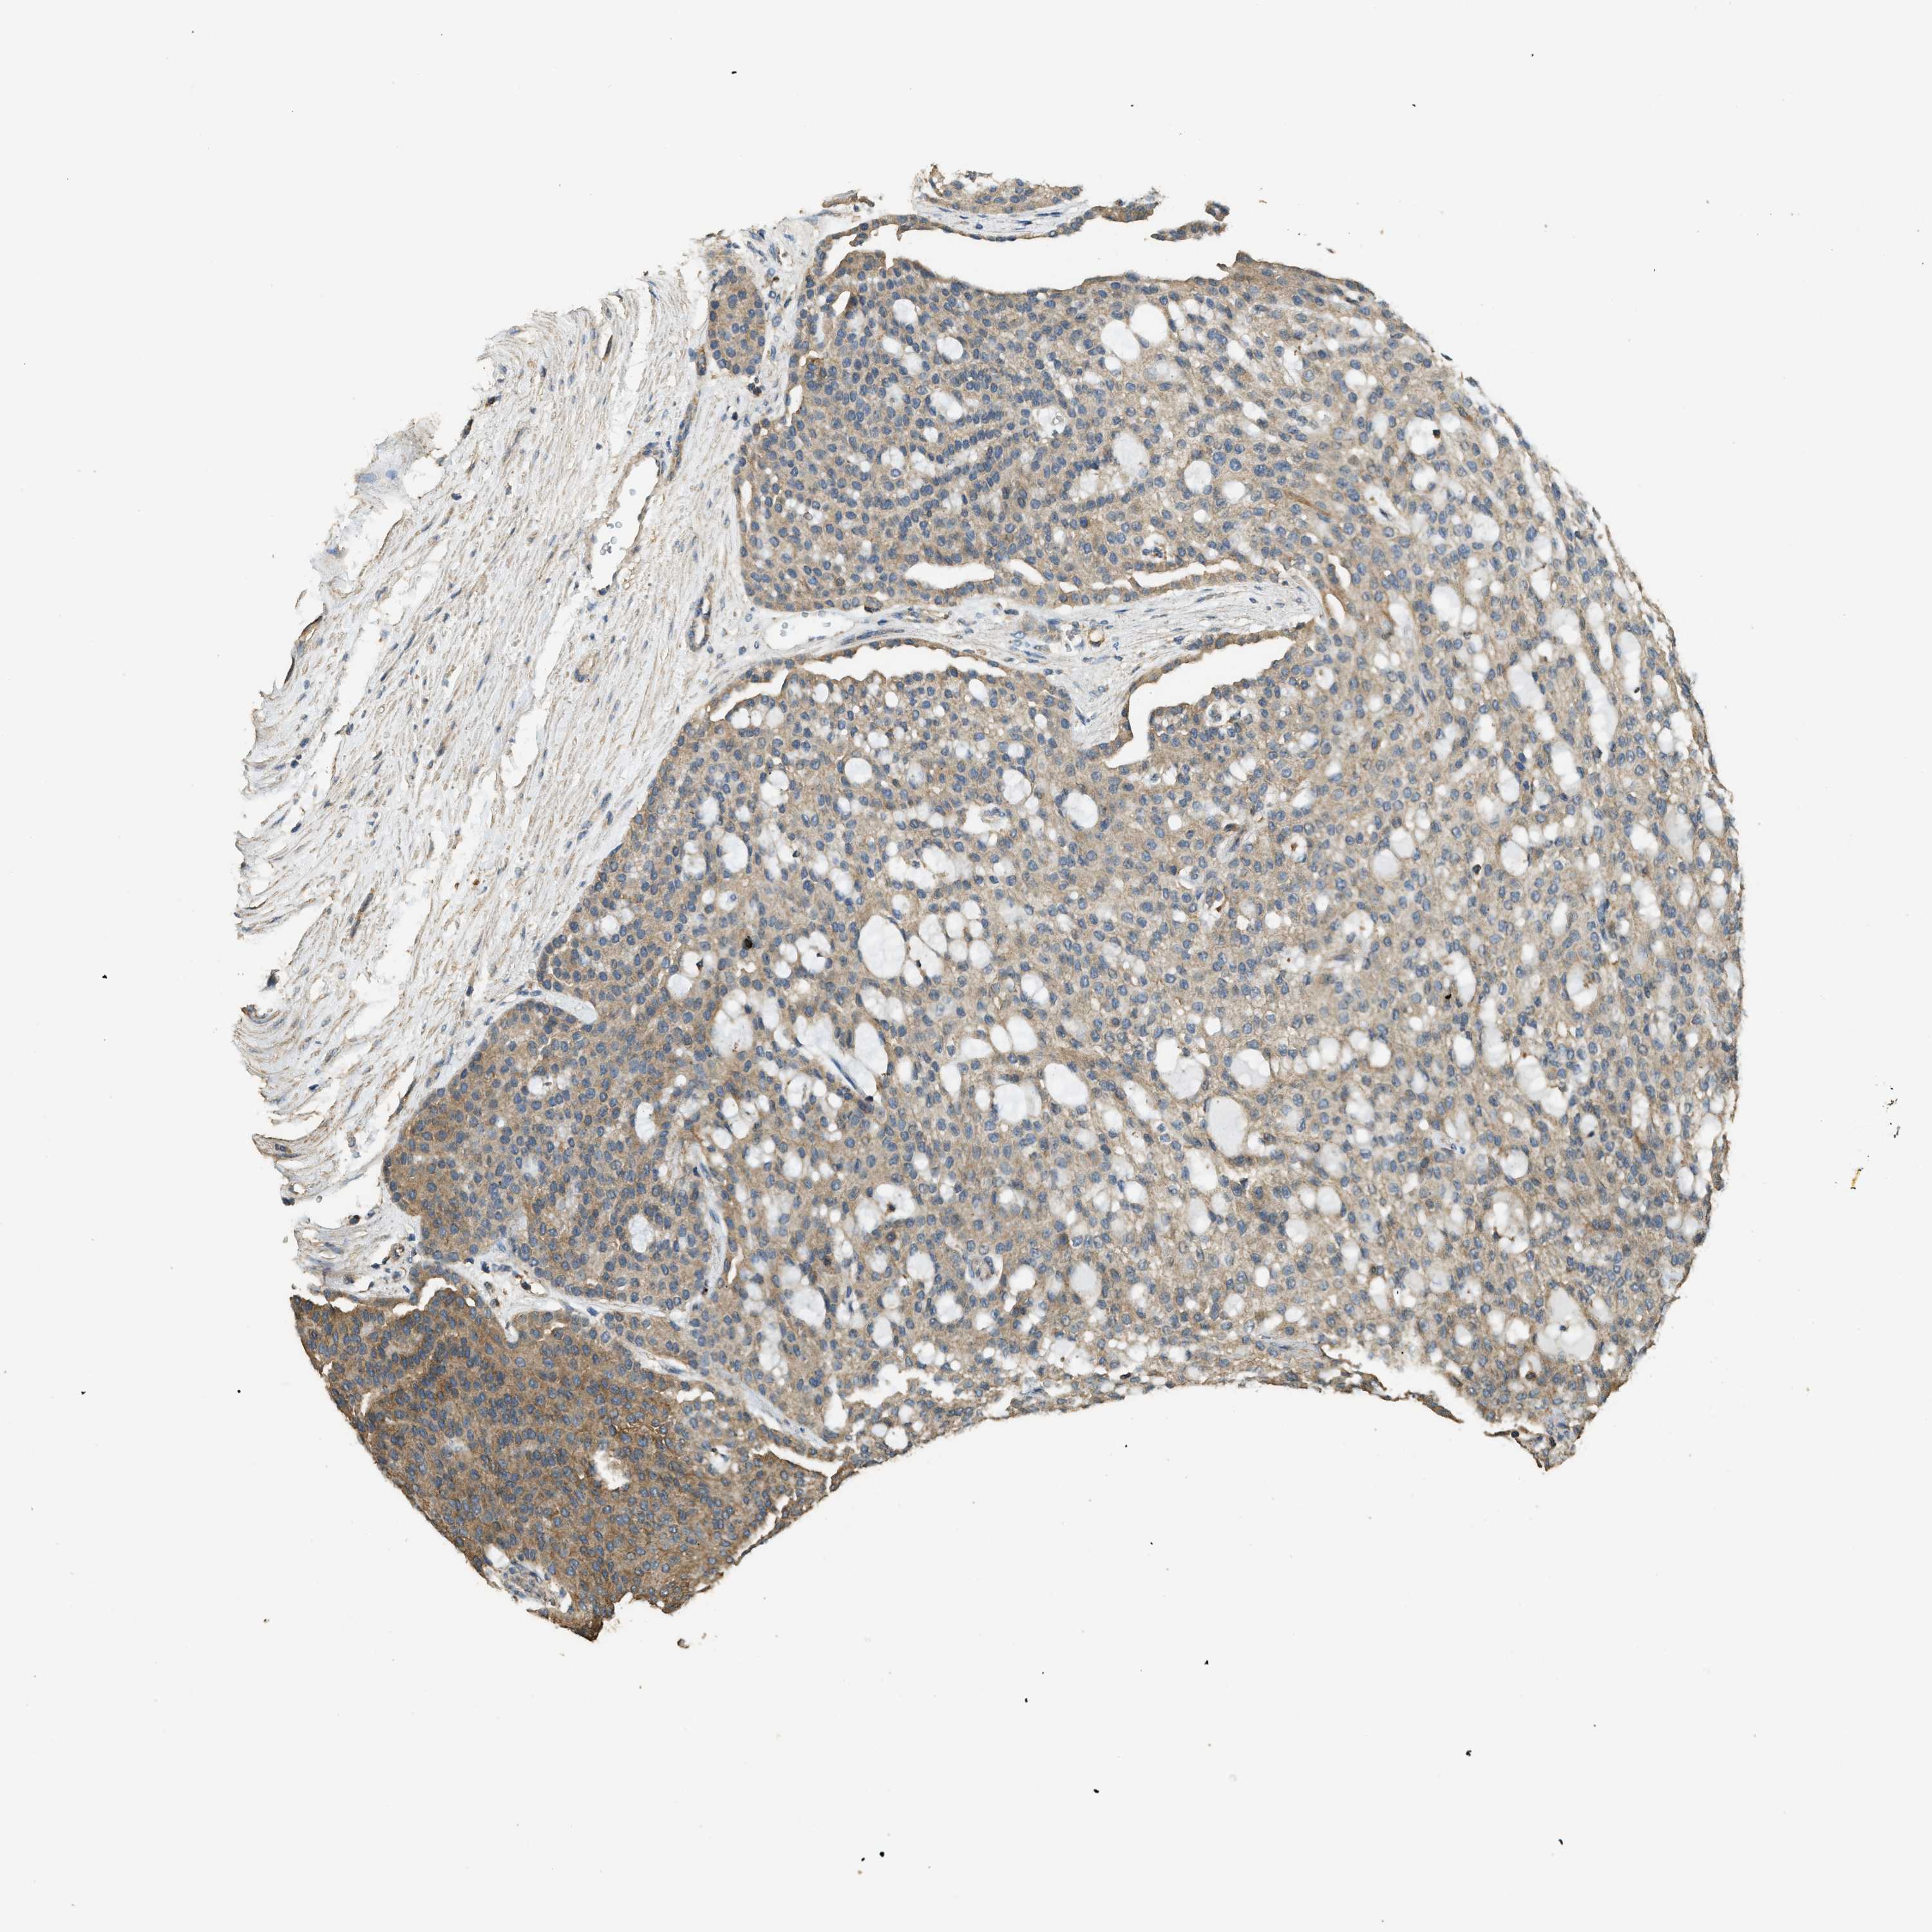

TCGA RNA samplesi

RNA-seq data is reported as average FPKM (number Fragments Per Kilobase of exon per Million reads), generated by the The Cancer Genome Atlas (TCGA) .

Normal distribution across the dataset is visualized with box plots, shown as median and 25th and 75th percentiles. Points are displayed as outliers if they are above or below 1.5 times the interquartile range. FPKM values of the individual samples are presented next to the box plot.

Average pTPM 32.6

Number of samples 100